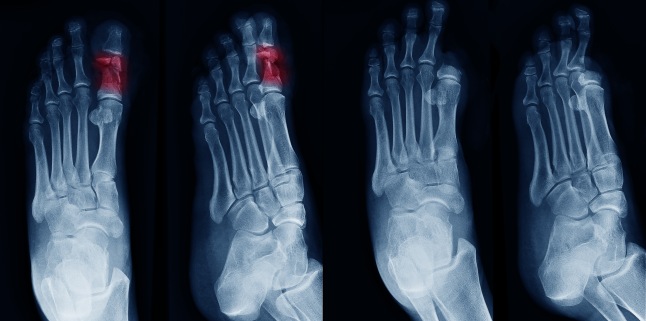

Prevalenta crescuta a acestei complicatii rezulta in cresterea morbiditatii, cu infectii recurente ale membrelor inferioare, ulceratii, si in final ajungand pana la amputatii. Din pacate, pacientii diabetici cu probleme la nivelul piciorului ocupa mai multe paturi de spital decat toti cei cu celelalte complicatii ale diabetului la un loc.

- polineuropatie distala simetrica: cel mai comun tip, deseori considerat sinonim cu neuropatia diabetica; se caracterizeaza prin pierderea progresiva a sensibilitatilor, urmata in cazuri grave de afectare motorie. Manifestarea tipica este in manusa sau in ciorap, cu amorteala, furnicaturi, senzatie de arsura, durere la atingere, chiar si crampe musculare, picioare nelinistite, scaderea fortei musculare, instabilitate la mers, deformarea piciorului (picior Charcot piciorul diabetic).

2. Ingrijirea piciorului diabeti: persoanele cu diabet zaharat trebuie sa faca o inspectie zilnica a picioarelor si sa fie atente la pielea aspra, crapaturi ale pielii, fisuri, formarea de bataturi la nivelul talpii si semne de infectie in jurul unghiilor sau intre degete. Odata instalata neuropatia, toata aceasta inspectie a piciorului trebuie sa fie si mai riguroasa, deoarece orice rana la nivelul picioarelor ar putea trece neobservata din cauza pierderii sensibilitatilor la acest nivel. Se recomanda purtarea de incaltaminte comoda, din piele naturala, cu calapod comod, care sa nu produca bataturi; sunt recomandate sosetele de bumbac care sa absoarba transpiratia, igiena zilnica a picioarelor cu apa si sapun, stergerea temeinica a piciorului inclusiv intre degete, pilirea unghiilor in locul taierii acestora. Persoanele cu diabet trebuie sa fie atente atunci cand merg desculte, fie in casa (pericol de accidentare, apa prea fierbinte care sa produca arsuri), cat si in afara casei (nisip fierbinte, spini etc.).